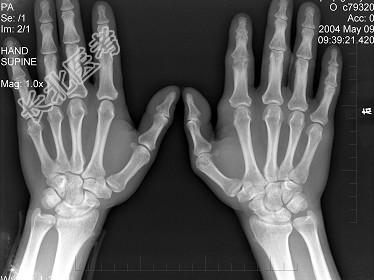

- 单项选择题男,19岁, 双手肿痛2年,晨僵, 结合图像,最可能诊断是 ( )

A、痛风

B、强直性脊柱炎

C、类风湿关节炎

D、退行性关节炎

E、未见异常